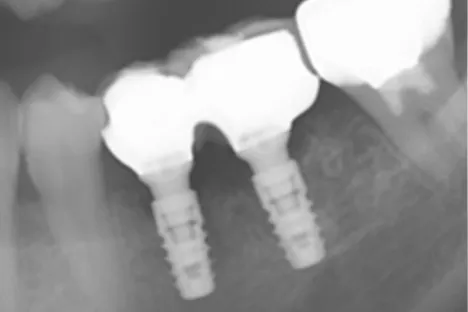

Dr.-Taniguchi_Fig.1

Fig. 1. Pre-operative: Subgingival caries at 35 and a vertical root fracture at 36 were observed.